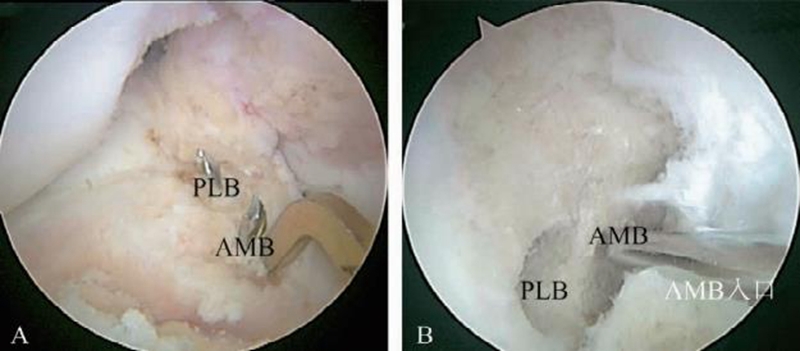

2.以骨嵴标志为参照的ACL四骨道解剖双束重建

可以说这是ACL四骨道双束重建术出现10年左右,双束重建技术基本成熟的标志。该技术因为是基于对ACL解剖的新研究成果设计的,因此可称为ACL的四骨道解剖双束重建技术。其特点是注重髁间窝外侧嵴(住院医师嵴)和束间嵴在前内束和后外束股骨骨道定位中的作用,使得前内束股骨骨道的定位更准确(图6)。但因为2012年Sasaki才发表了ACL股骨Footprint直接止点致密区的组织学结果,2017年Robert Smigielski才发表了Ribbon止点特征,该时期双束重建代表性技术往往有前内束股骨骨道稍低而后外束股骨骨道过低的问题。

图6 以髁间窝外侧嵴(住院医师嵴)和内侧髁间嵴为参照的解剖双束重建术中股骨和胫骨的骨道定位

A.以胫骨平台内侧髁间嵴为解剖标志的ACL双束重建的胫骨骨道定位方法;B.以髁间窝外侧嵴为解剖标志的ACL双束重建的股骨骨道定位方法。PLB:后外束;AMB:前内束

该时期的胫骨骨道还是处于以ACL胫骨止点足印区为参照的阶段。总体前内束和后外束的胫骨骨道定位均偏外,但前、后位置没有明显问题。